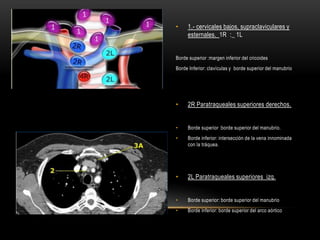

• 1.- cervicales bajos, supraclaviculares y

esternales. 1R :_ 1L

Borde superior :margen inferior del cricoides

Borde Inferior: clavículas y borde superior del manubrio

• 2R Paratraqueales superiores derechos.

• Borde superior :borde superior del manubrio.

• Borde inferior: intersección de la vena innominada

con la tráquea.

• 2L Paratraqueales superiores izq.

• Borde superior: borde superior del manubrio

• Borde inferior: borde superior del arco aórtico

• 1.- cervicalesbajos, supraclaviculares y esternales. 1R :_ 1L Borde superior :margen inferior del cricoides Borde Inferior: clavículas y borde superior del manubrio • 2R Paratraqueales superiores derechos. • Borde superior :borde superior del manubrio. • Borde inferior: intersección de la vena innominada con la tráquea. • 2L Paratraqueales superiores izq. • Borde superior: borde superior del manubrio • Borde inferior: borde superior del arco aórtico

• #34 Supraclavicular nodes1. Low cervical, supraclavicular and sternal notch nodesFrom the lower margin of the cricoid to the clavicles andthe upper border of the manubrium.The midline of the trachea serves as border between 1Rand 1L.Superior MediastinalNodes 2-42R. UpperParatracheal2R nodes extend to the left lateral border of the trachea.From upper border of manubrium to the intersection ofcaudal margin of innominate (left brachiocephalic) veinwiththetrachea.2L. UpperParatrachealFrom the upper border of manubrium to the superiorborder of aorticarch.2L nodes are located to the left of the left lateral border ofthetrachea.3A. Pre-vascularThese nodes are not adjacent to the trachea like thenodes in station 2, but they are anterior to the vessels.3P. Pre-vertebralNodes not adjacent to the trachea like the nodes in station2, but behind the esophagus, which is prevertebral.4R. LowerParatrachealFrom the intersection of the caudal margin of innominate(left brachiocephalic) vein with the trachea to the lowerborder of the azygos vein.4R nodes extend from the right to the left lateral border ofthetrachea.4L. LowerParatrachealFrom the upper margin of the aortic arch to the upper rimof the left main pulmonary artery.

• #35 Los nodulos de la estacion 2 l se encuentran limitados por el borde superior del manubrio y el borde superior del arco aortico2R. RightUpperParatracheal2R nodes extend to the left lateral border of the trachea.Upper border: upper border of manubrium.Lower border: intersection of caudal margin of innominate(left brachiocephalic) vein with the trachea.2L. LeftUpperParatrachealUpper border: upper border of manubrium.Lower border: superior border of aortic arch.On the left a station 2 node in front of the trachea, i.e. a2R-node.